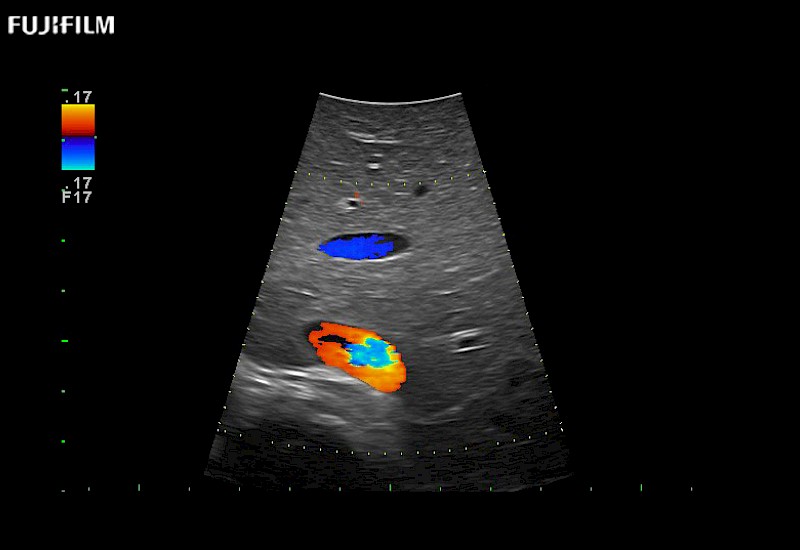

For precise surgical oncology ultrasound imaging, Fujifilm Healthcare offers premium level solutions that include:

for use during open and laparoscopic procedures: Tumor localization & staging, Ablation, Resection, Biopsy, Transplant, Abdominal exploration, Robotic surgery

Our dedication to Surgical Oncology allows us to offer superior image quality, outstanding system reliability and intuitive use of cutting edge technology.